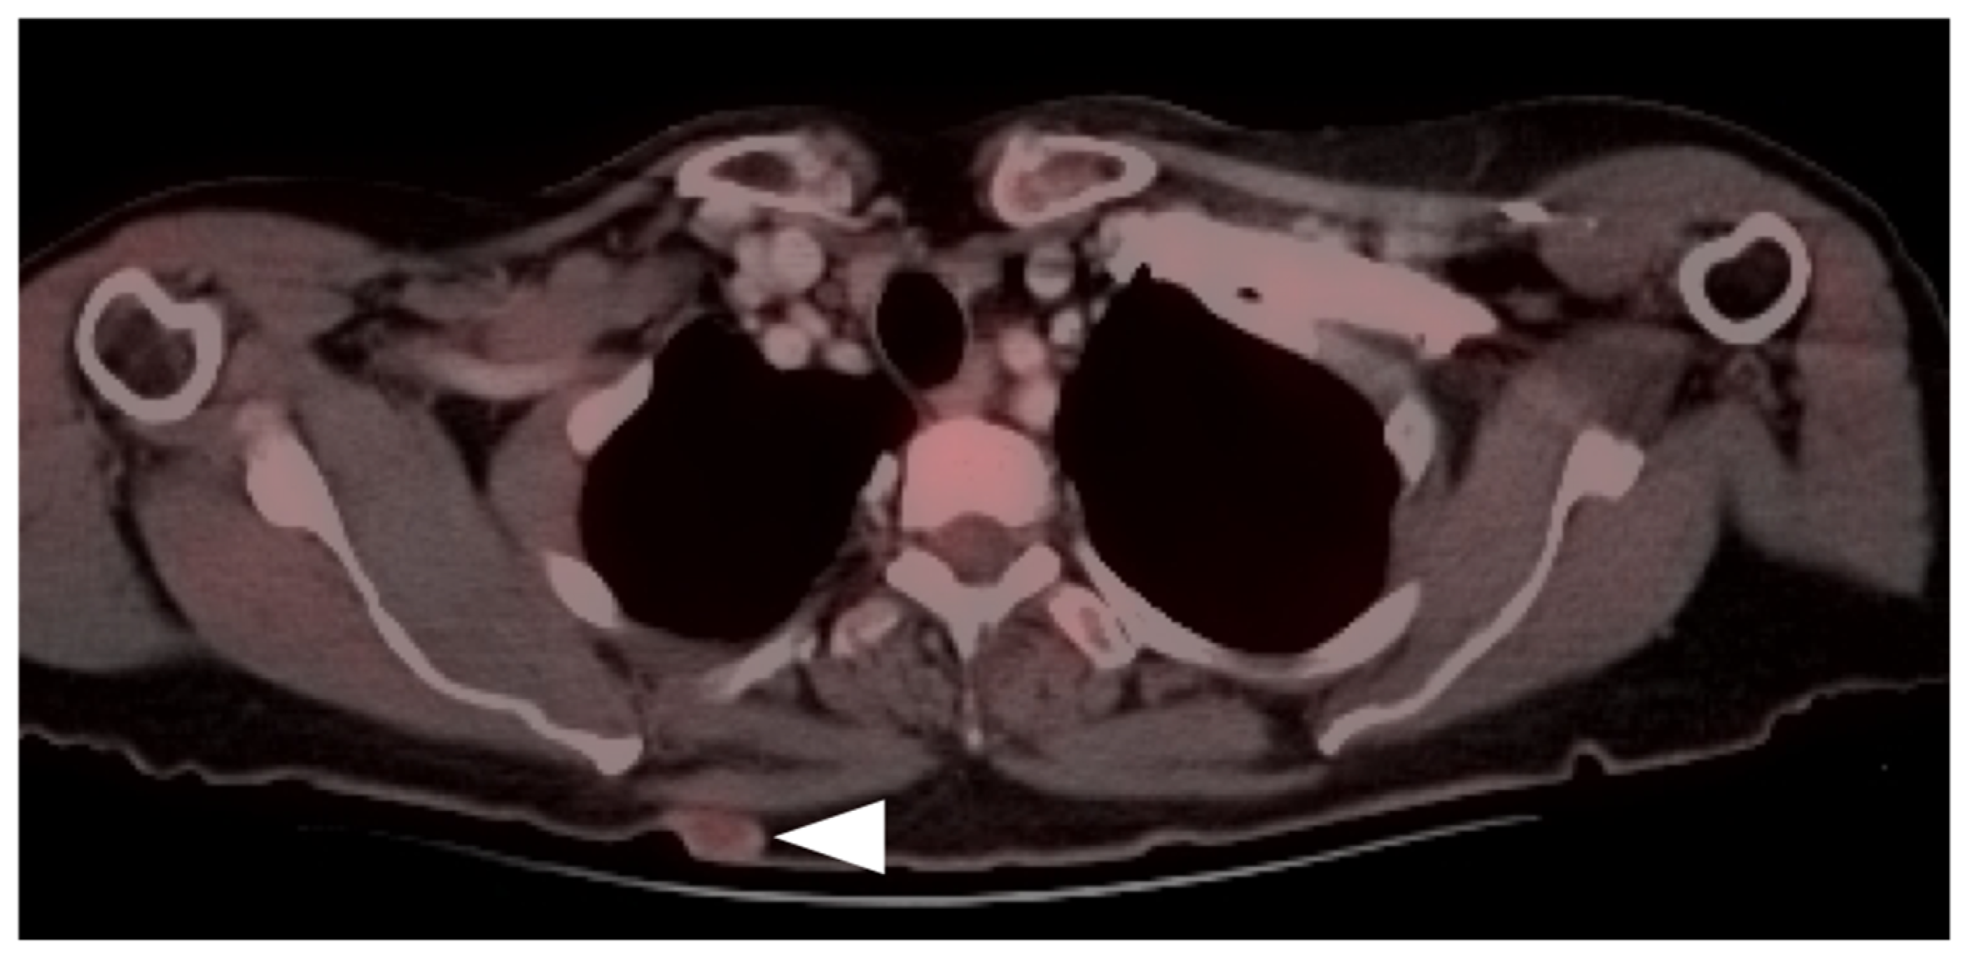

- Qiu, S.; Zou, S.; Cheng, S.; Song, S.; Zhu, X. Positive FAPI PET/CT in a Bilateral Mammary Angiosarcoma Patient with Less Impressive FDG PET/CT Images. Clin. Nucl. Med. 2022. [Google Scholar] [CrossRef]

- Camoni, L.; Albano, D. Contrast-enhanced 18F-FDG PET/CT to differentiate primary cardiac lymphoma from primary cardiac angiosarcoma. J. Nucl. Cardiol. 2021, 1–3. [Google Scholar] [CrossRef]